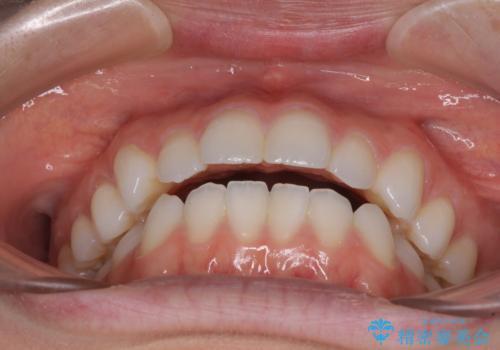

上下前歯が接触しない オープンバイトをインビザラインで改善

- 前歯の上下スペースによる食べにくさを気にして来院された患者様です。

インビザラインにより上下の前歯の隙間を閉じていくこととしました。

上下の奥歯を圧下させるようにすることで、前歯を接触させるように計画しました。